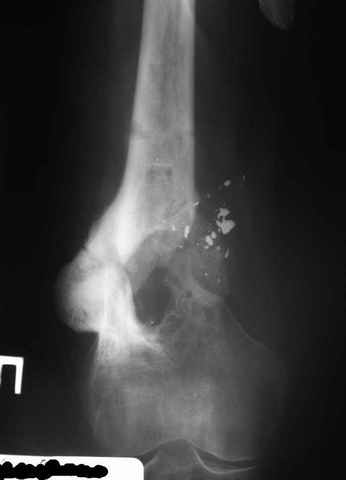

Рефрактур уж точно можно будет не опасаться, а за несколько месяцев даже при отсутствии заполнения костью по всей окружности, этот обходной "мостик" упрочнится и возьмет на себя нагрузку. В приложении пример такого рода "эндопротезирования диафиза", прошло больше 3 лет.

Пациентка, страдающая еще и инсулинозависимым диабетом, не хромает, работает инженером.